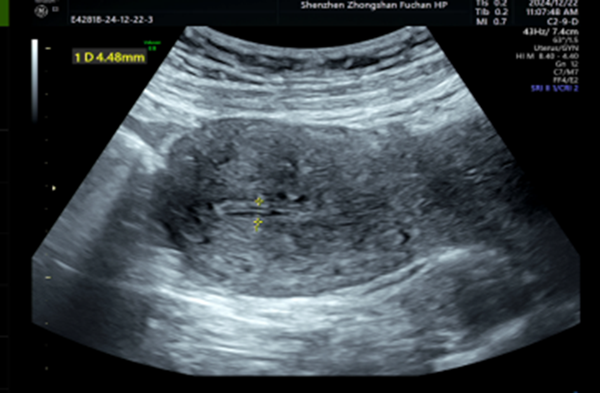

我一看报告,写着“粘膜下子宫肌瘤,5cm大小”。考虑到她还打算要宝宝,我们决定用宫腔镜来切除这个肌瘤——这种方式对子宫伤害最小,不影响以后怀孕。